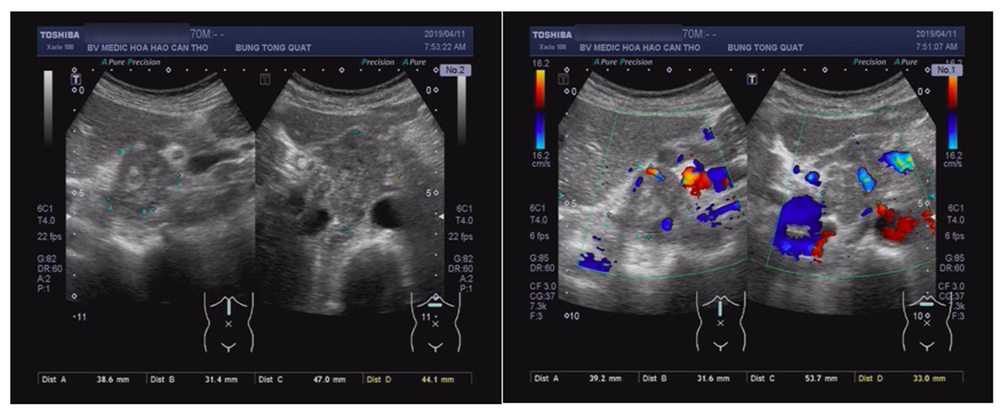

Siêu âm

Dày vách thực quản đoạn tâm vị 15mm, chùm hạch lớn 5cm vùng cạnh đầu và thân tụy.